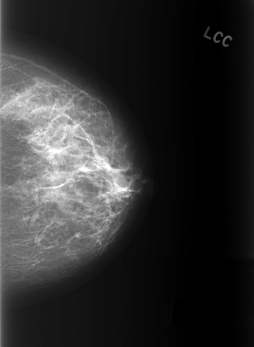

ics_version 1.0 filename C-0402-1 DATE_OF_STUDY 9 1 1996 PATIENT_AGE 49 FILM FILM_TYPE REGULAR DENSITY 2 DATE_DIGITIZED 15 10 1998 DIGITIZER LUMISYS LASER SEQUENCE LEFT_CC LINES 5552 PIXELS_PER_LINE 4056 BITS_PER_PIXEL 12 RESOLUTION 50 NON_OVERLAY LEFT_MLO LINES 5440 PIXELS_PER_LINE 3984 BITS_PER_PIXEL 12 RESOLUTION 50 NON_OVERLAY RIGHT_CC LINES 5640 PIXELS_PER_LINE 3800 BITS_PER_PIXEL 12 RESOLUTION 50 OVERLAY RIGHT_MLO LINES 5448 PIXELS_PER_LINE 4000 BITS_PER_PIXEL 12 RESOLUTION 50 OVERLAY |